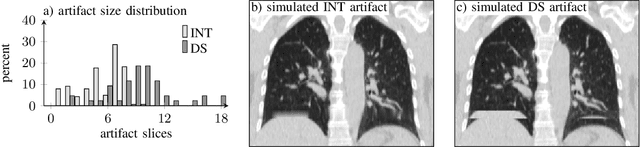

Abstract:4D CT imaging is an essential component of radiotherapy of thoracic/abdominal tumors. 4D CT images are, however, often affected by artifacts that compromise treatment planning quality. In this work, deep learning (DL)-based conditional inpainting is proposed to restore anatomically correct image information of artifact-affected areas. The restoration approach consists of a two-stage process: DL-based detection of common interpolation (INT) and double structure (DS) artifacts, followed by conditional inpainting applied to the artifact areas. In this context, conditional refers to a guidance of the inpainting process by patient-specific image data to ensure anatomically reliable results. Evaluation is based on 65 in-house 4D CT data sets of lung cancer patients (48 with only slight artifacts, 17 with pronounced artifacts) and the publicly available DIRLab 4D CT data (independent external test set). Automated artifact detection revealed a ROC-AUC of 0.99 for INT and 0.97 for DS artifacts (in-house data). The proposed inpainting method decreased the average root mean squared error (RMSE) by 60% (DS) and 42% (INT) for the in-house evaluation data (simulated artifacts for the slight artifact data; original data were considered as ground truth for RMSE computation). For the external DIR-Lab data, the RMSE decreased by 65% and 36%, respectively. Applied to the pronounced artifact data group, on average 68% of the detectable artifacts were removed. The results highlight the potential of DL-based inpainting for the restoration of artifact-affected 4D CT data. Improved performance of conditional inpainting (compared to standard inpainting) illustrates the benefits of exploiting patient-specific prior knowledge.